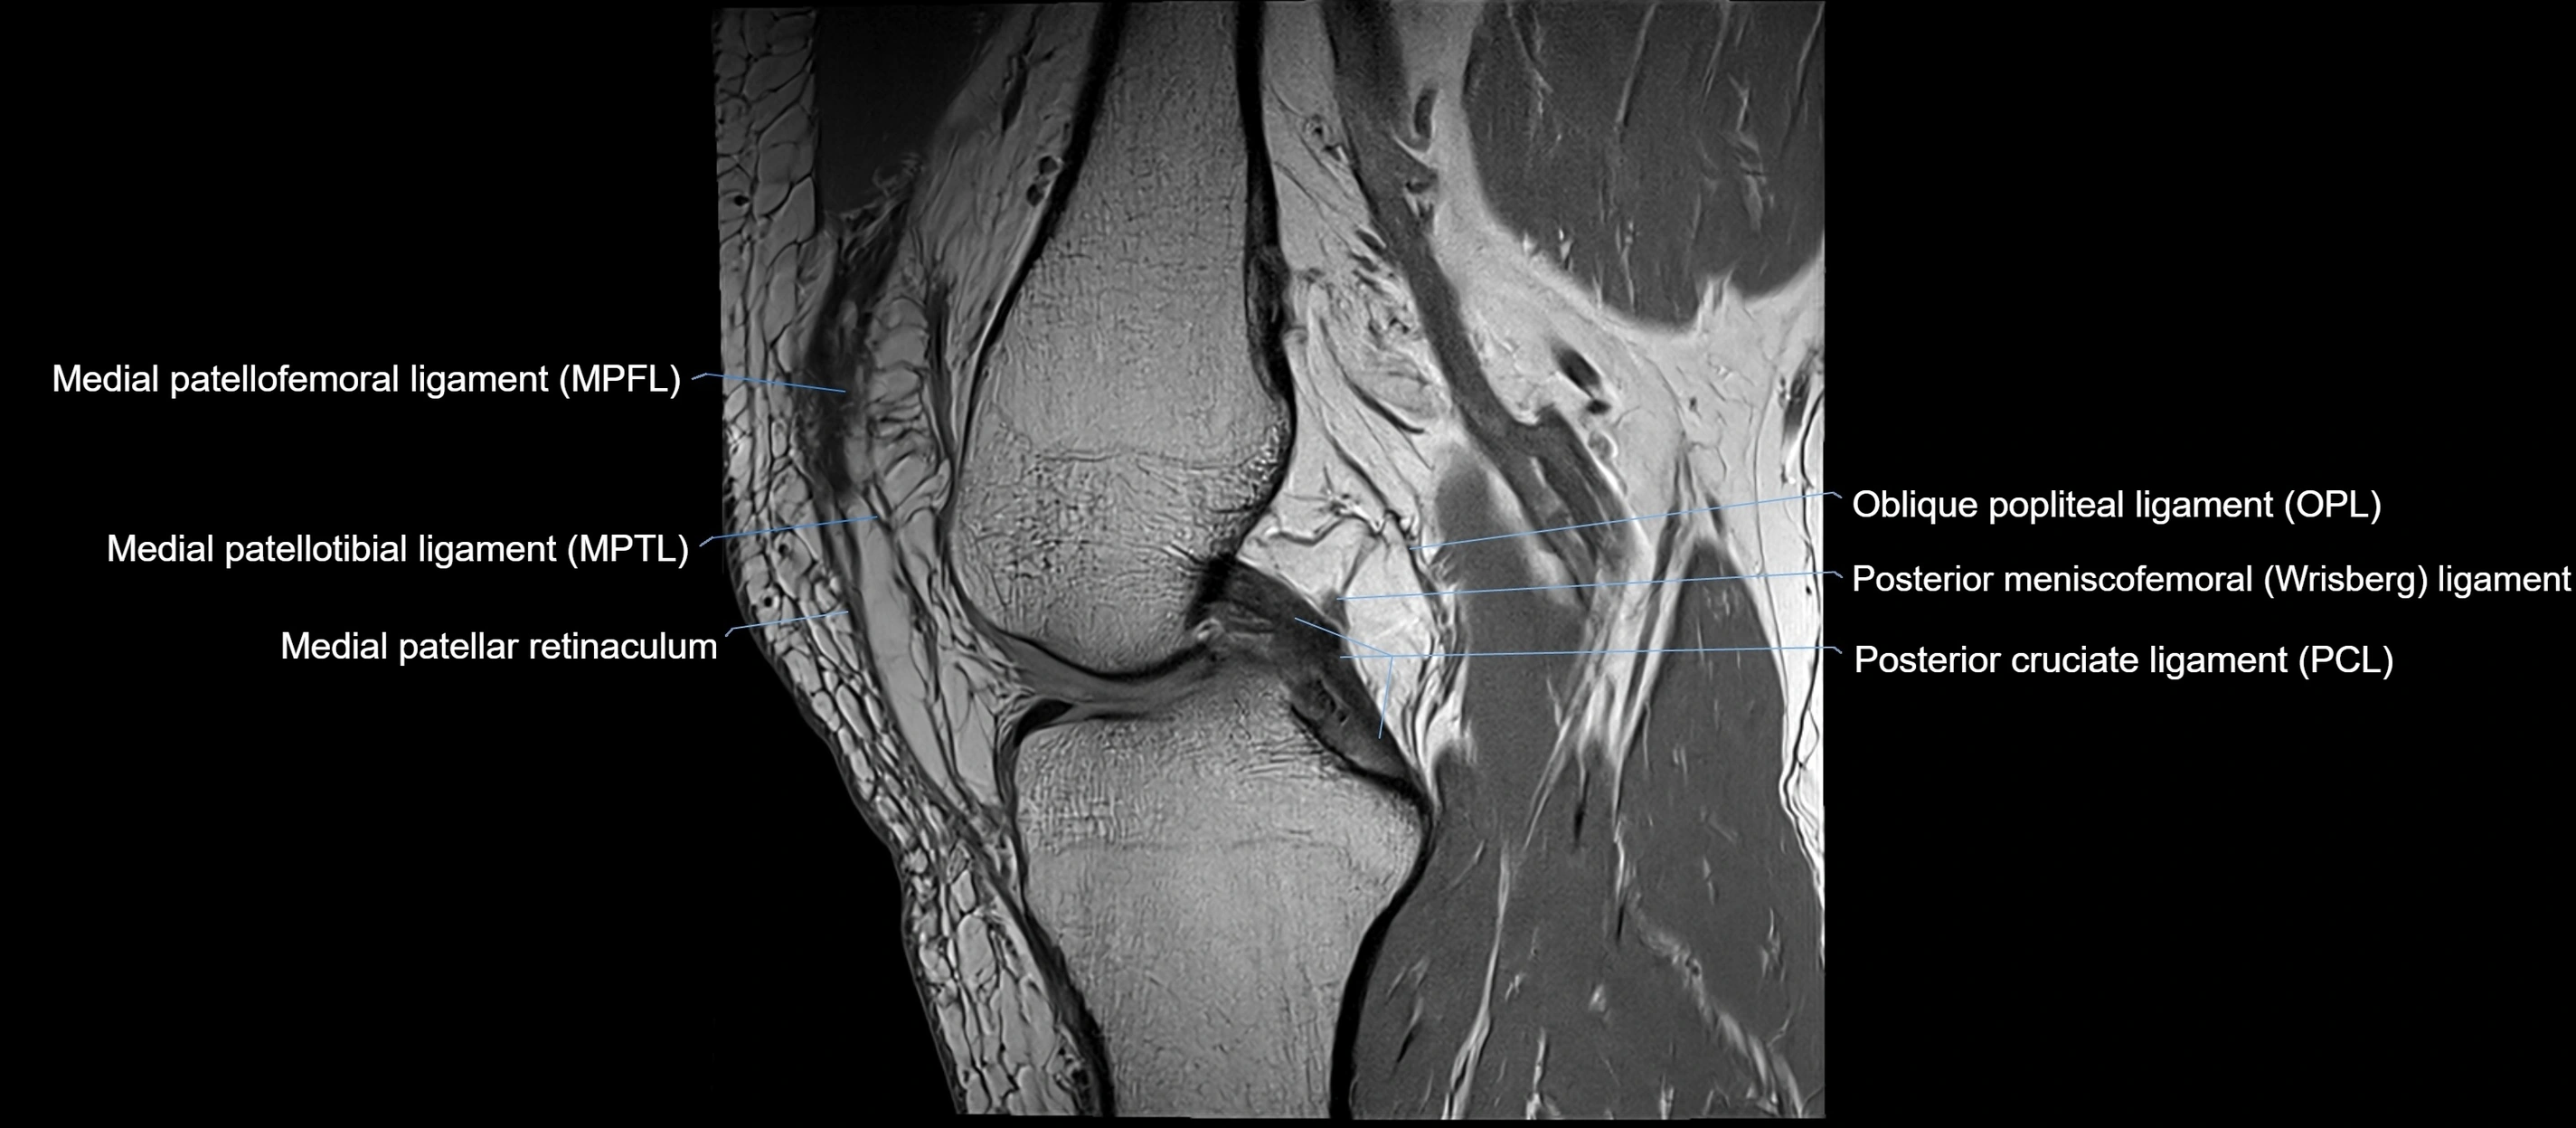

MRI images

image